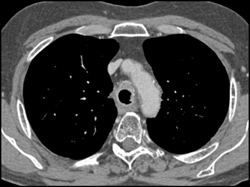

Stent in Distal Trachea- See Next Case